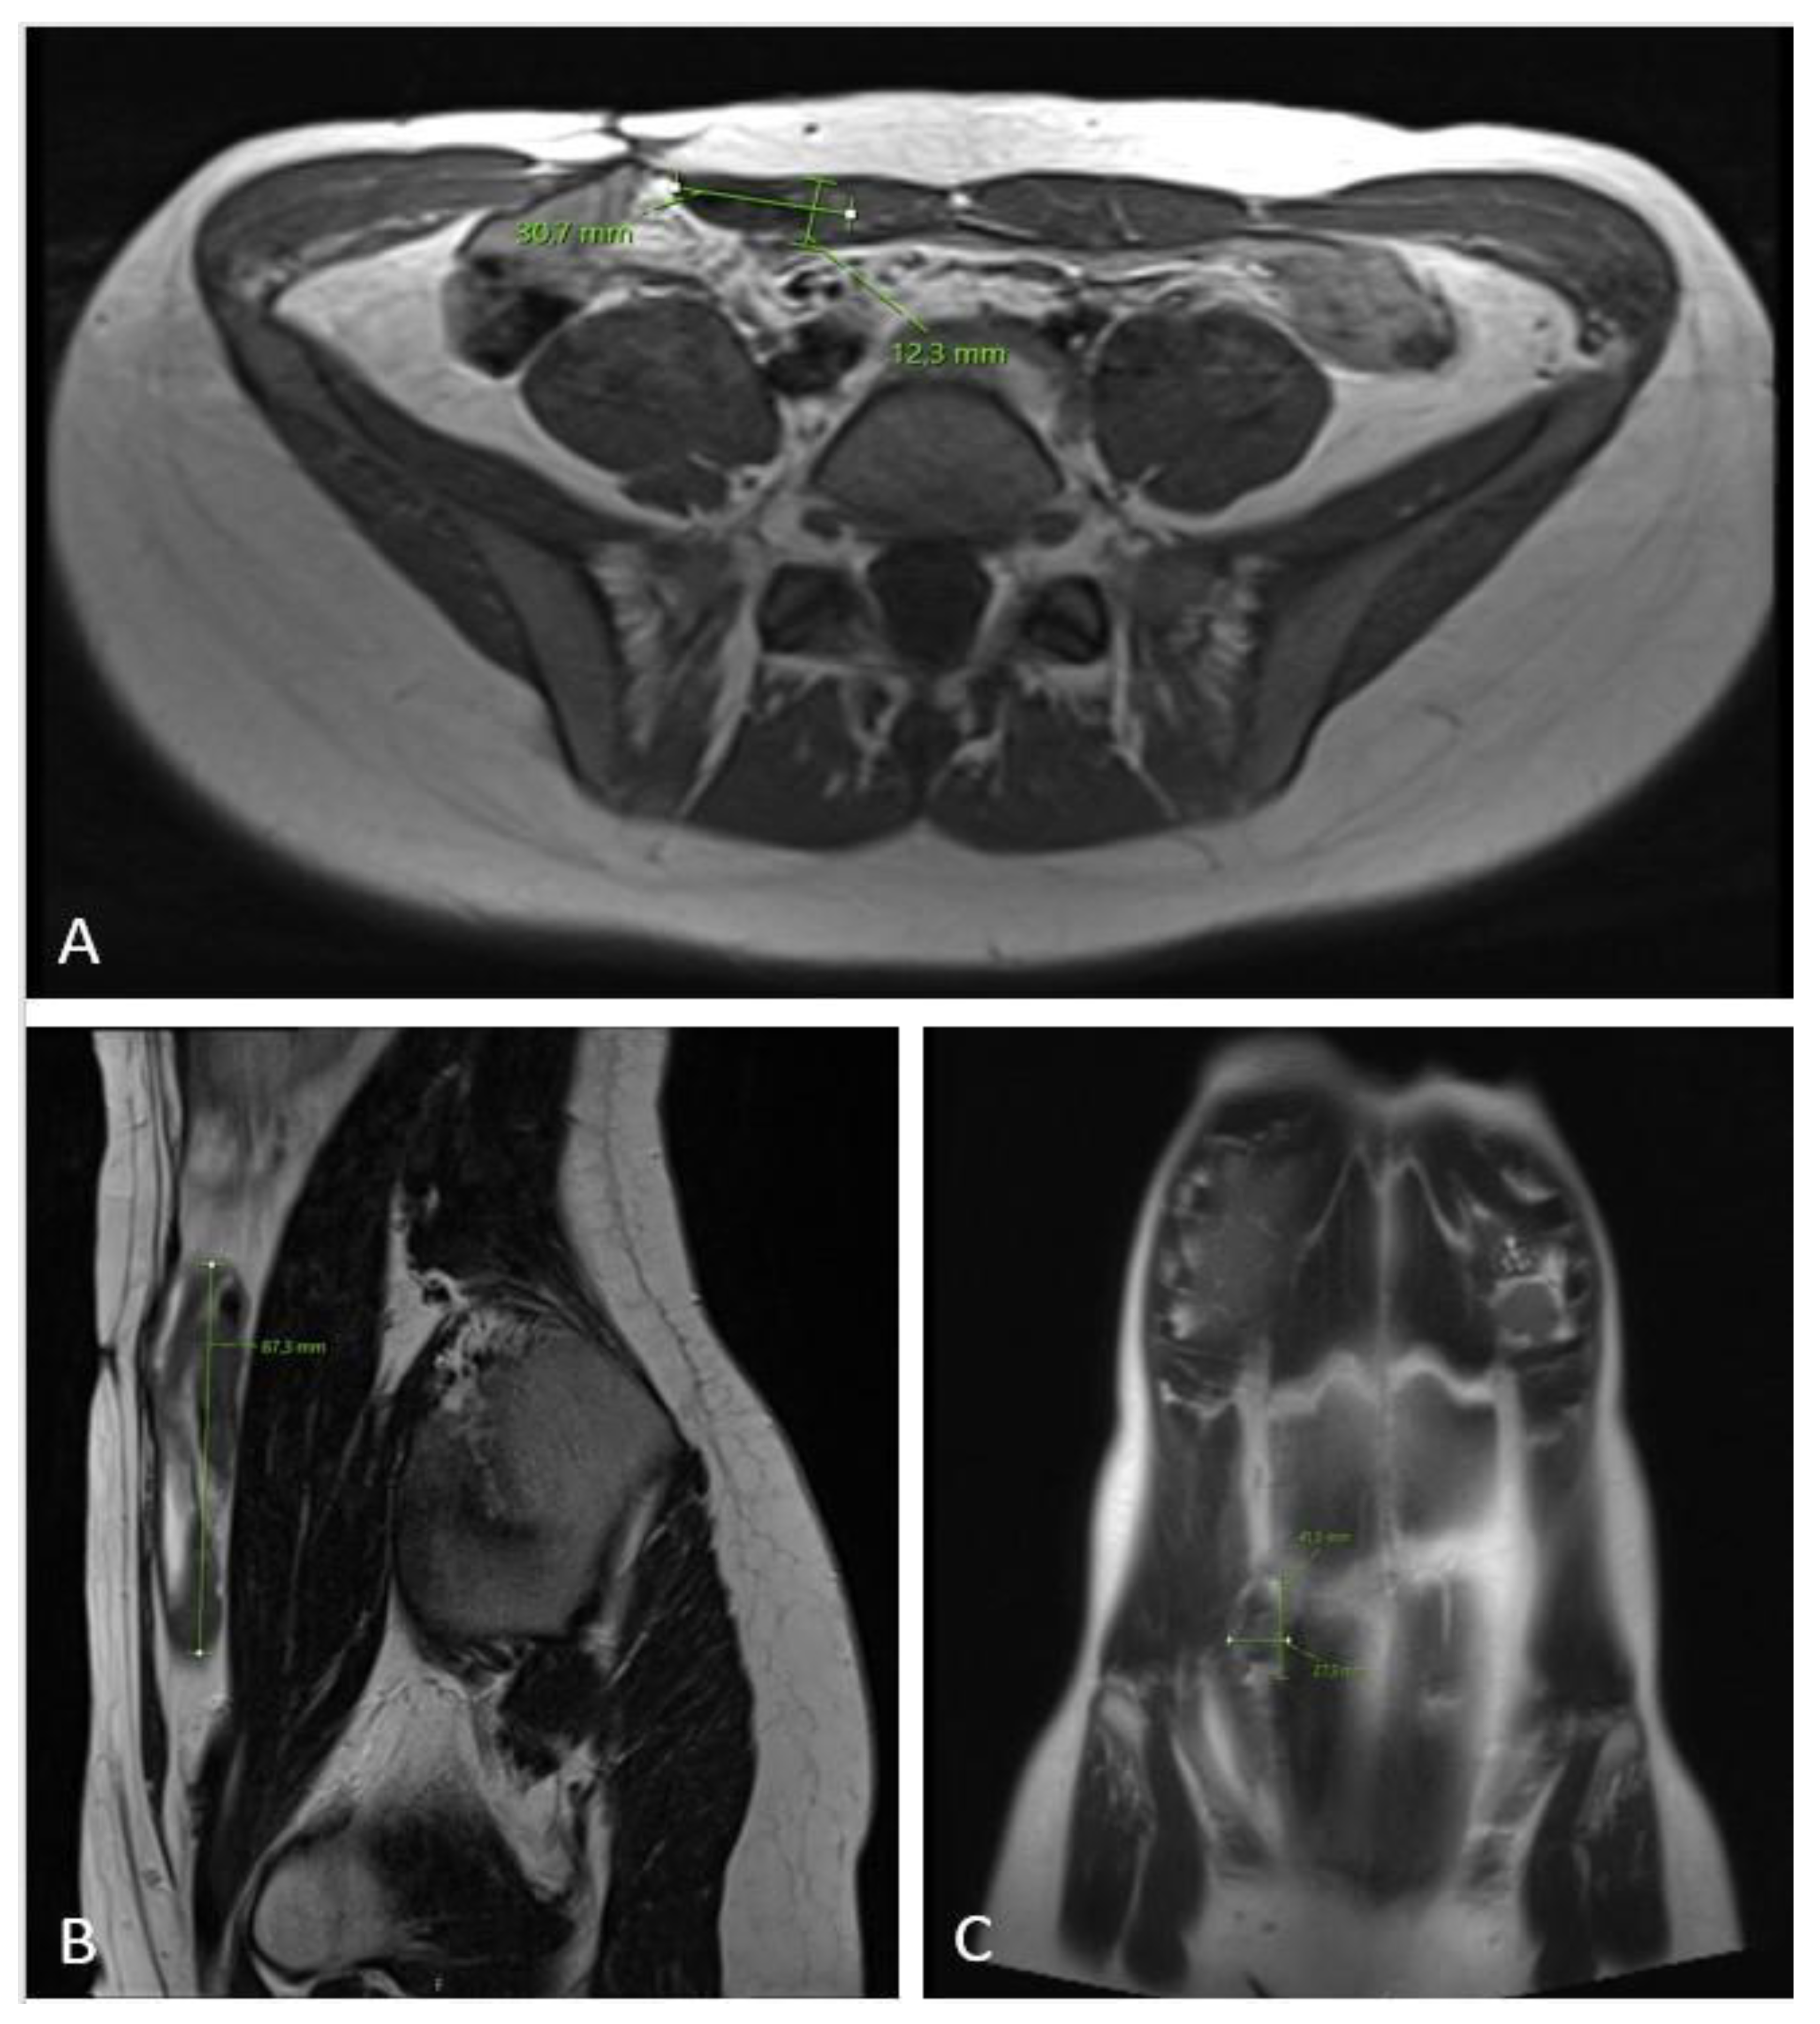

Figure 6.

MRI scan ((A)—axial plane; (B)—sagittal plane; (C)—coronal plane) 12 months after chemotherapy showing significant tumor regress, sized only 1.2 × 3.7 × 8.7 cm.